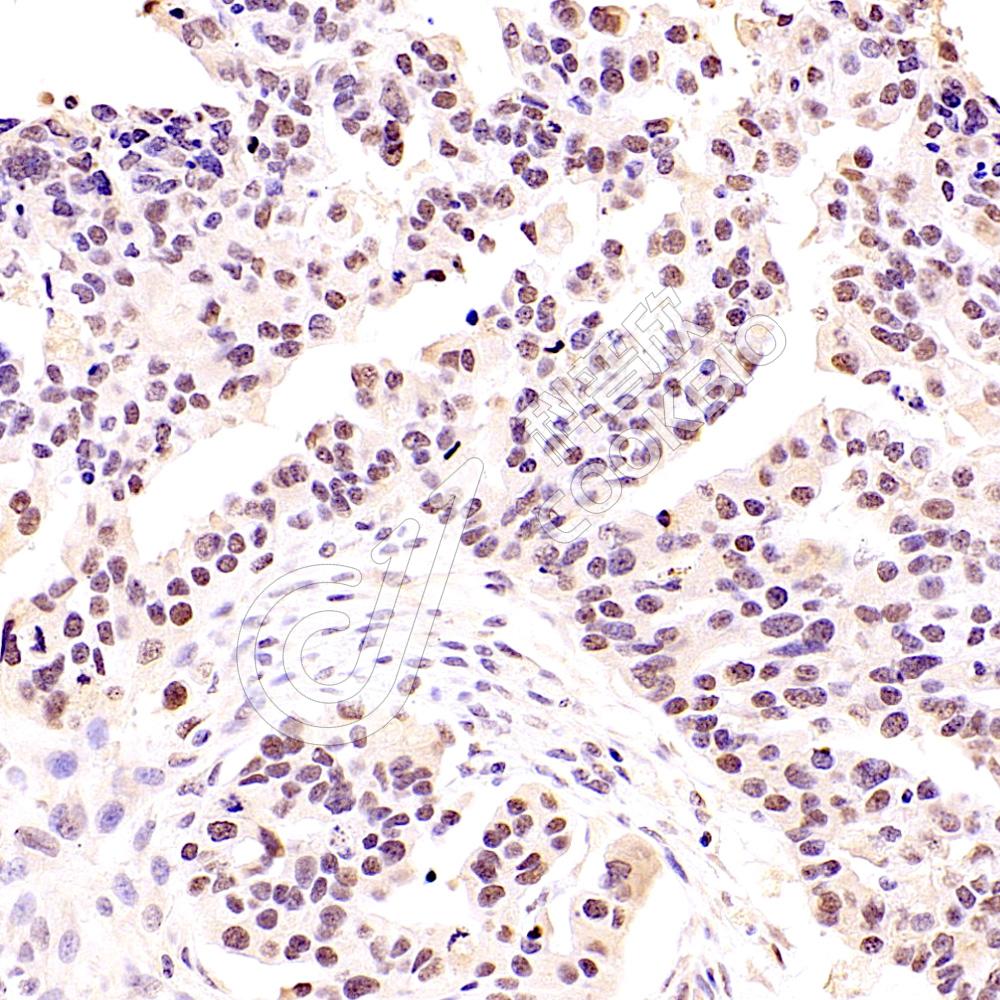

IHC检测Sall4蛋白(货号 K5464382).

样品: 人精原细胞瘤, 4%多聚甲醛 (货号KSG1101) 固定12-24小时.

抗原修复: 柠檬酸抗原修复液(干粉, pH 6.0) (KSG1201), 高压锅均匀喷气计时2分钟.

—抗: 1: 800稀释, 4℃ 孵育过夜.

二抗: S-vision免疫组化多聚二抗(山羊抗小鼠), 即用型(货号KB3903), 室温孵育20分钟.